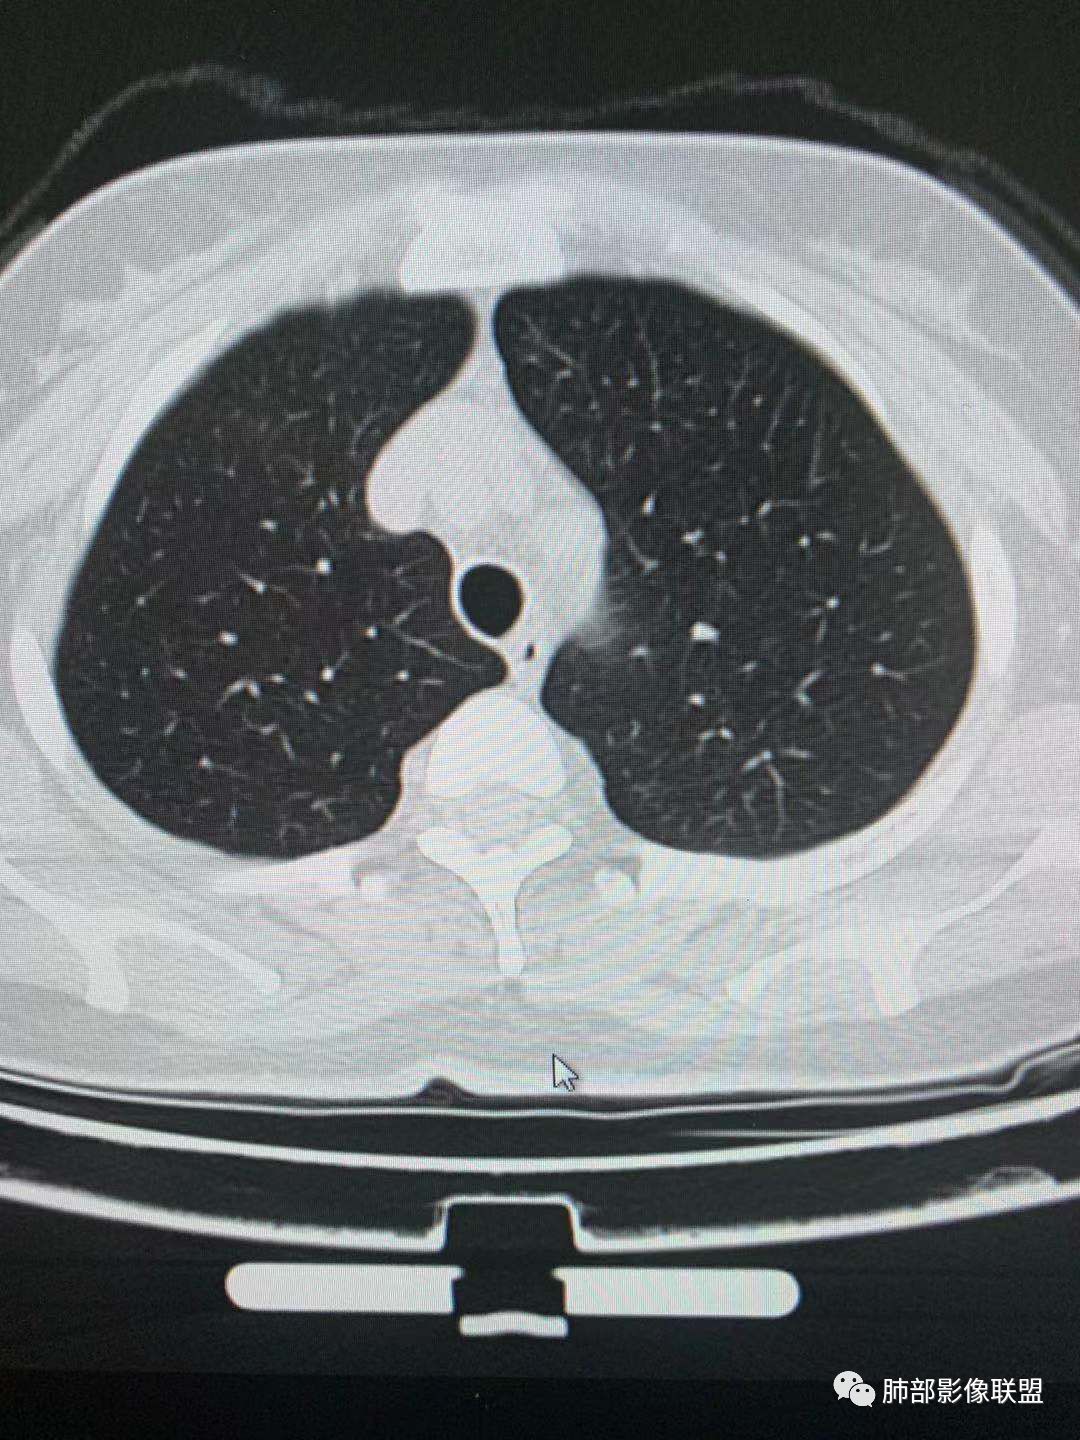

左肺上叶实性结节,光滑,支气管血管贴边,晕,强化持续。两年前就有,考虑psp。另外左肺上叶纵膈侧胸膜下及中带两处混合磨玻璃结节,考虑原位和微浸润可能,需要随访看看。

左肺上叶实性结节,边缘光滑清晰,血管贴边,渐进性延迟强化,密度均匀,考虑PSP.

左肺上叶实性结节,边缘光滑清晰,血管贴边,渐进性延迟强化,密度均匀,考虑PSP.但是强化幅度不够,需要鉴别早期肺癌 医学百科网 | YxBaike.Com

总共三个结节 医学百科网 | YxBaike.Com

最大的靠后,有血管贴边征,渐进性明显强化,考虑PSP可能大

靠前部中等大小结节考虑MIA

靠中部最小的那个结节AAH或者慢性炎症均有可能 医学百科网 | YxBaike.Com

中年女性,左肺上叶实性圆形结节,边缘有晕,血管及支气管贴边,强化尚均匀,渐进性明显强化,考虑为PSP可能